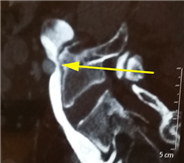

CTV示:左髂总静脉起始部受压,该处髂总静脉管腔受压变形呈线性狭窄,符合cockett综合征改变。

入院左髂静脉CT成像:左髂总静脉起始部受压、狭窄明显